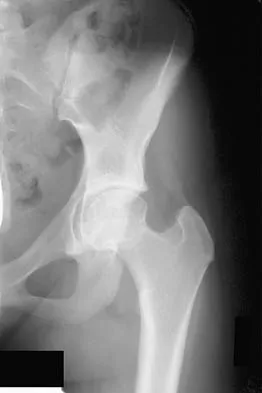

Figures 9a and 9b show the radiographs of a 12-year-old girl who has had right hip pain for the past 4 months. She reports that the pain is so severe that she is unable to walk and is now using a wheelchair. Examination reveals pain with any attempted range of motion. Management should include

In addition to mild hip dysplasia, the radiograph shows an osteoblastic lesion of the right ilium. The patient's symptoms are much more severe than is typical for late hip dysplasia. MRI can determine the extent of the lesion in the bone and soft tissues. Following work-up and biopsy, the patient was diagnosed with Ewing's sarcoma. Springfield DS, Gebhardt MC: Bone and soft tissue tumors, in Morrissy RT, Weinstein SL (eds): Lovell and Winter's Pediatric Orthopaedics, ed 5. Philadelphia, PA, Lippincott Williams and Wilkins, 2001, pp 507-518, 542-544.